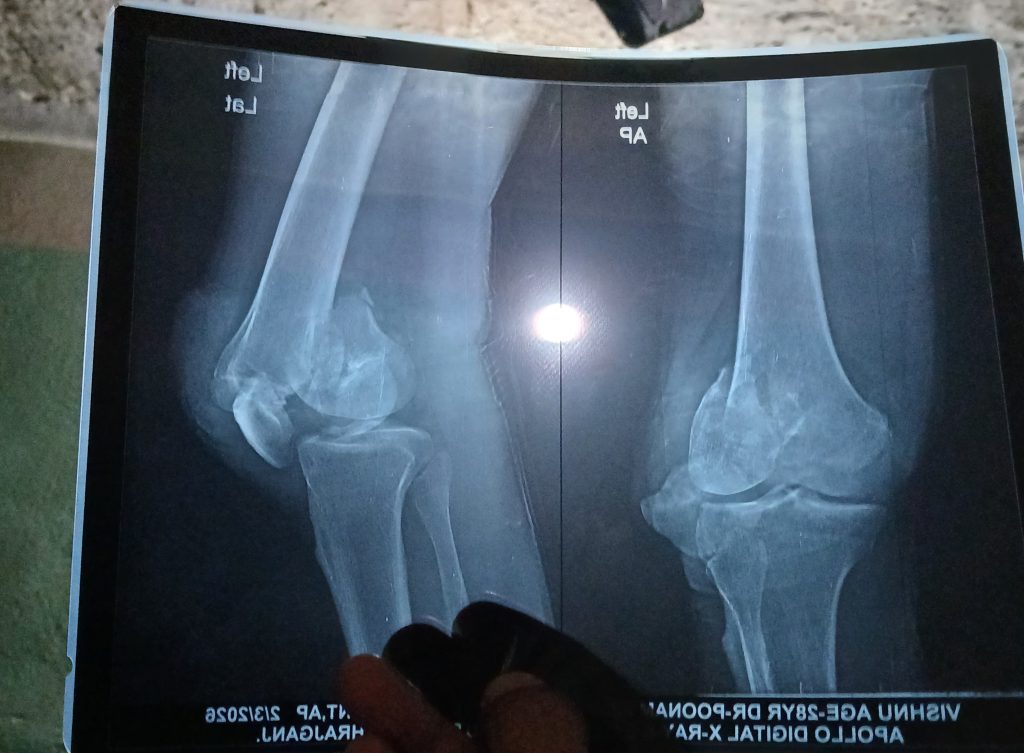

भैरहवा, माघ २३ — रुपन्देही जिल्लाको ओमसतिया गाउँपालिका–३ दुमदुमवाका स्थानीयवासी विष्णु अर्याल सवारी दुर्घटनामा परेर खुट्टामा गम्भीर चोट लागेपछि हाल उपचाररत रहनुभएको छ। दुर्घटनापछि उहाँको अवस्था गम्भीर बनेको र चिकित्सकको सल्लाहअनुसार लामो समयसम्म उपचार आवश्यक पर्ने देखिएको छ।